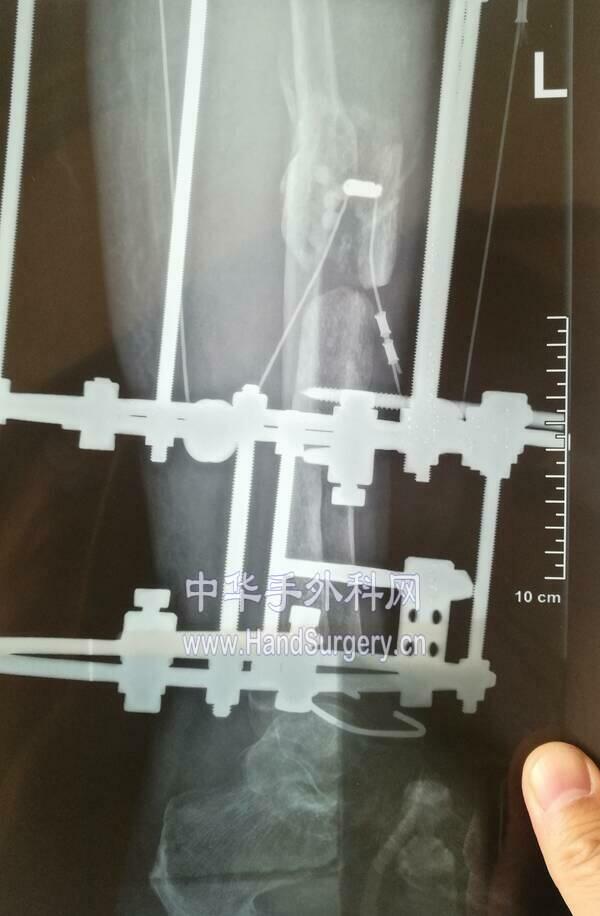

单边外架双段截骨骨搬运

IMG_20190318_200814.jpg

IMG_20190318_123403.jpg

IMG_20190319_103709.jpg

IMG_20190318_091940.jpg

软牵引骨滑移